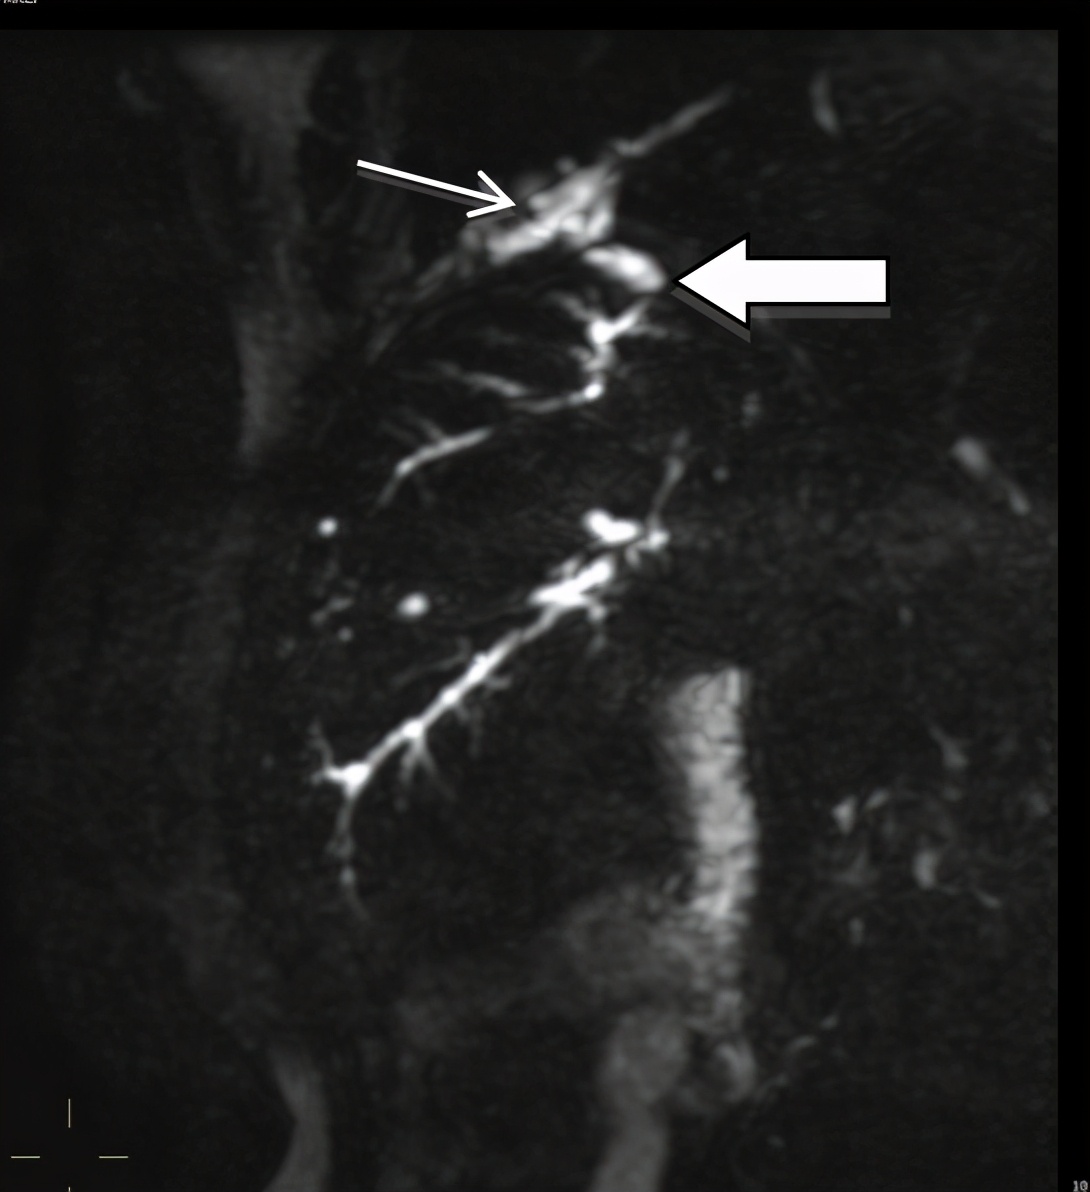

带着这些疑问,我们进一步完善了相关检查。将痰液送检胆红素,结果显示胆红素显著升高,这一结果印证了我们的推测,金黄色痰液就是胆汁,高度提示存在胆管-支气管瘘可能。为进一步确证,行磁共振胰胆管成像(MRCP)检查提示「肝右叶近膈面处异常信号,考虑感染,肝脓肿可能性大,累积膈肌,并与右下肺相通,肝右叶下极大片异常信号,考虑肝癌可能,部分肝内胆管稍扩张」(图5)。

图5:2012年2月21日我院MRCP:肝右叶近膈面处异常信号(粗箭头处),考虑感染,肝脓肿可能性大,累积膈肌,并与右下肺(细箭头处为支气管树)相通。